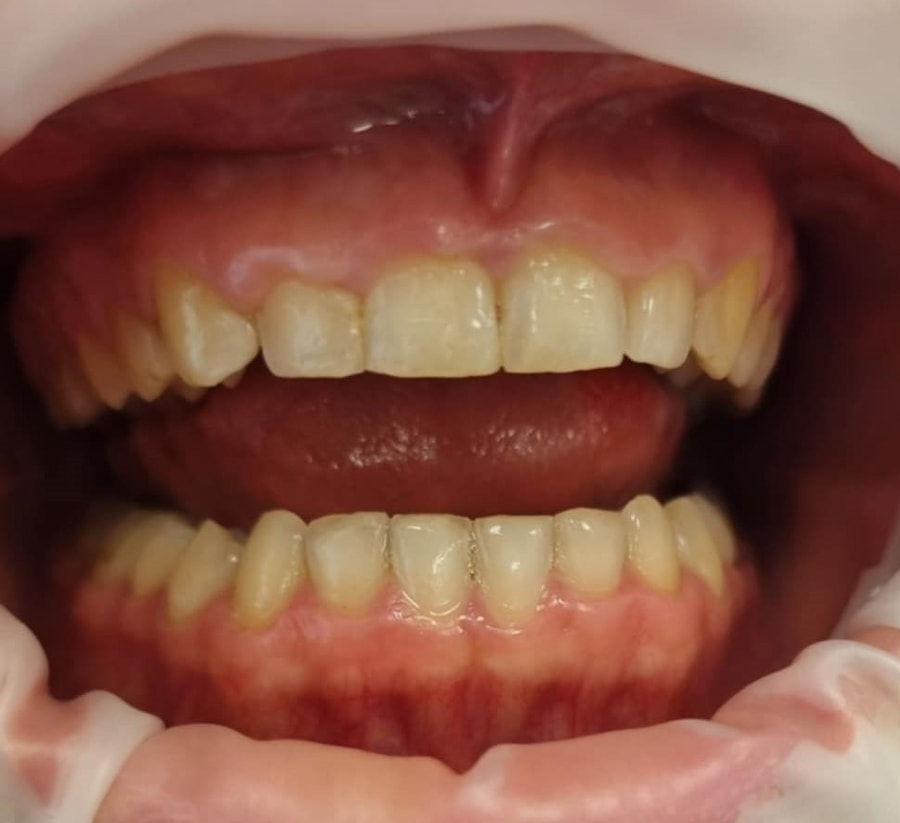

Przykład zabiegu gingiwektomi

Przed

Zabieg gingiwektomi przed